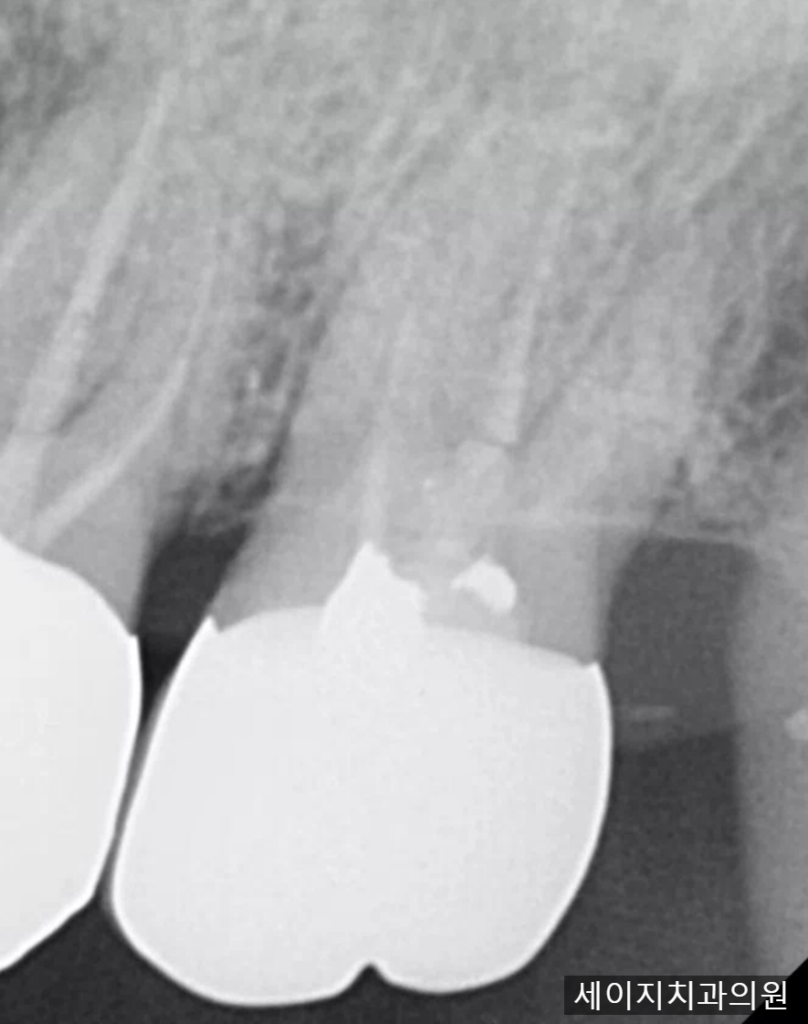

2024. 04. 30(포스트 + 코어 + 치관연장술을 적용하여 크라운을 다시 씌운 모습)

치아는 다시 회복 되었으며 크라운 까지 적용하여 기존의 교합 관계에 맞게 조정해드렸습니다. 충치로 인해 자연치아가 부러진 경우에 무조건 발치를 해야 한다고 생각하는 분들이 많은 것 같습니다. 물론 상황에 따라 종합적인 판단으로 고려해야 한다고 생각합니다.

환자분의 전반적인 구강관리능력과, 교합관계 등을 고려하여 자연치아 보존을 가장 먼저 고려해보고 만일 환자분의 교합관계가 특수하여 치료 후에도 예지성 없는 치료가 될 경우라면 조심스레 발치의 가능성을 이야기 드리고 있습니다.